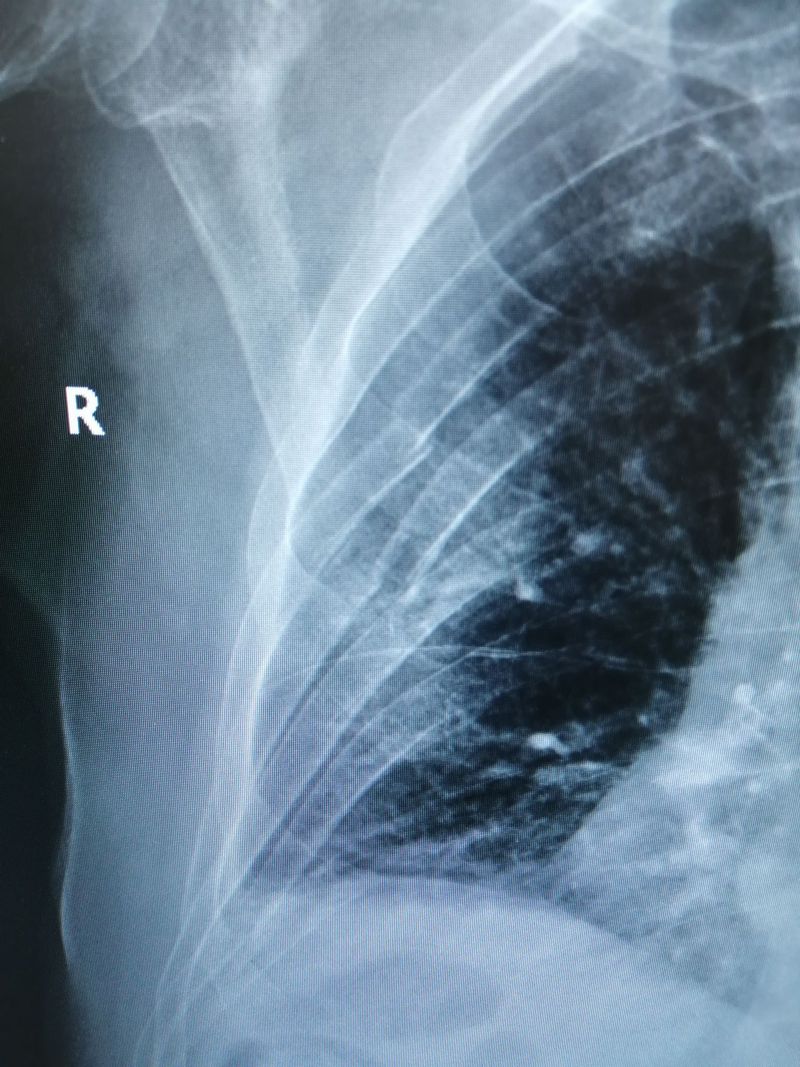

Ribs AP View

Chest pain that is worse with breathing in.

Fracture

Ribs